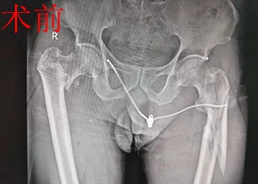

日前,刘老伯在家做事时,不慎从3米高的二楼坠落到一楼,当时顿感双侧髋部疼痛,无法站立。家人见状,赶紧将其送往娄底市骨伤医院。结合急诊相关检查,诊断为:右股骨粗隆粉碎性骨折,左股骨上段粉碎性骨折,随后转入髋股膝胫科住院治疗。髋股膝胫科主任、副主任医师黄才平向患者及家属分析,考虑刘老伯患有糖尿病,且双侧股骨均有粉碎性骨折,若保守治疗骨折粉碎严重、容易畸形、卧床时间久,容易发生肺部感染、褥疮等并发症,而手术治疗可以达到减轻痛苦、加速康复、提高生活质量的目的。

经患者家属同意后,髋股膝胫科专家团队为刘老伯精心制定了严谨的手术及快速康复方案。经过紧张有序的术前准备,在麻醉科、手术室的通力协作下,由黄才平主任为首,在李志勇、邓亚军医师的配合下,为刘老伯行“右股骨粗隆粉碎性骨折闭合复位PFNA内固定术﹢左股骨上段粉碎性骨折闭合复位加长型PFNA内固定术”。手术历时两个半小时,出血量仅200毫升,手术非常成功。